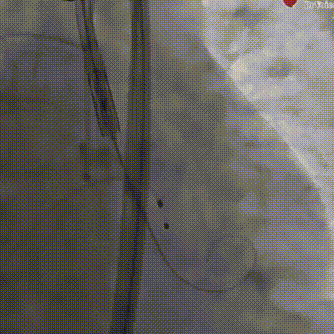

术中猪尾导管至左室测定术前左心室及升主动脉收缩舒张压分别为222/7、111/40mmHg;成功组装瓣膜并经输送系统送入20mm SAPIEN 3瓣膜主动脉,顺利过弓并成功跨瓣;

成功跨瓣

瓣膜经输送系统顺利过弓